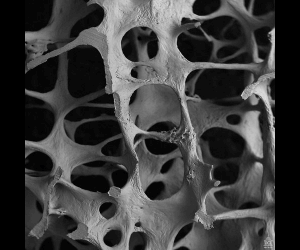

골다공증은 뼈의 밀도와 강도가 감소하여 뼈가 약해지는 질환입니다. 정상적인 뼈는 밀도와 구조가 강하여 외부의 충격이나 압력에도 견딜 수 있습니다. 그러나 골다공증 환자는 일상적인 활동이나 경부의 손상으로도 골절이 생길 수 있습니다. 주로 고령자에게서 나타나며 여성들이 주로 많은 영향을 받습니다. 에스트로겐 호르몬의 감소로 폐경을 하게 되면 여성들은 골다 공증이 생기게 됩니다. 이는 에스트로겐 호르몬이 뼈 형성에 중요한 역할을 하기 때문입니다. 하지만 남성들도 골다공증이 발생할 수 있습니다.